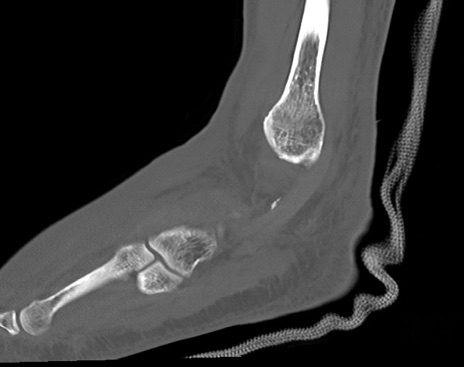

症例37 左足関節CT(矢状断像)

左足関節CT